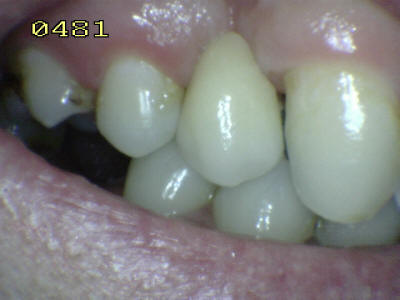

Aspecto vestibular del r3emanente dentario Eliminada la caries, micro-arenado con óxido de aluminio y grabado total con acido ortofosforico (Flechas blancas)